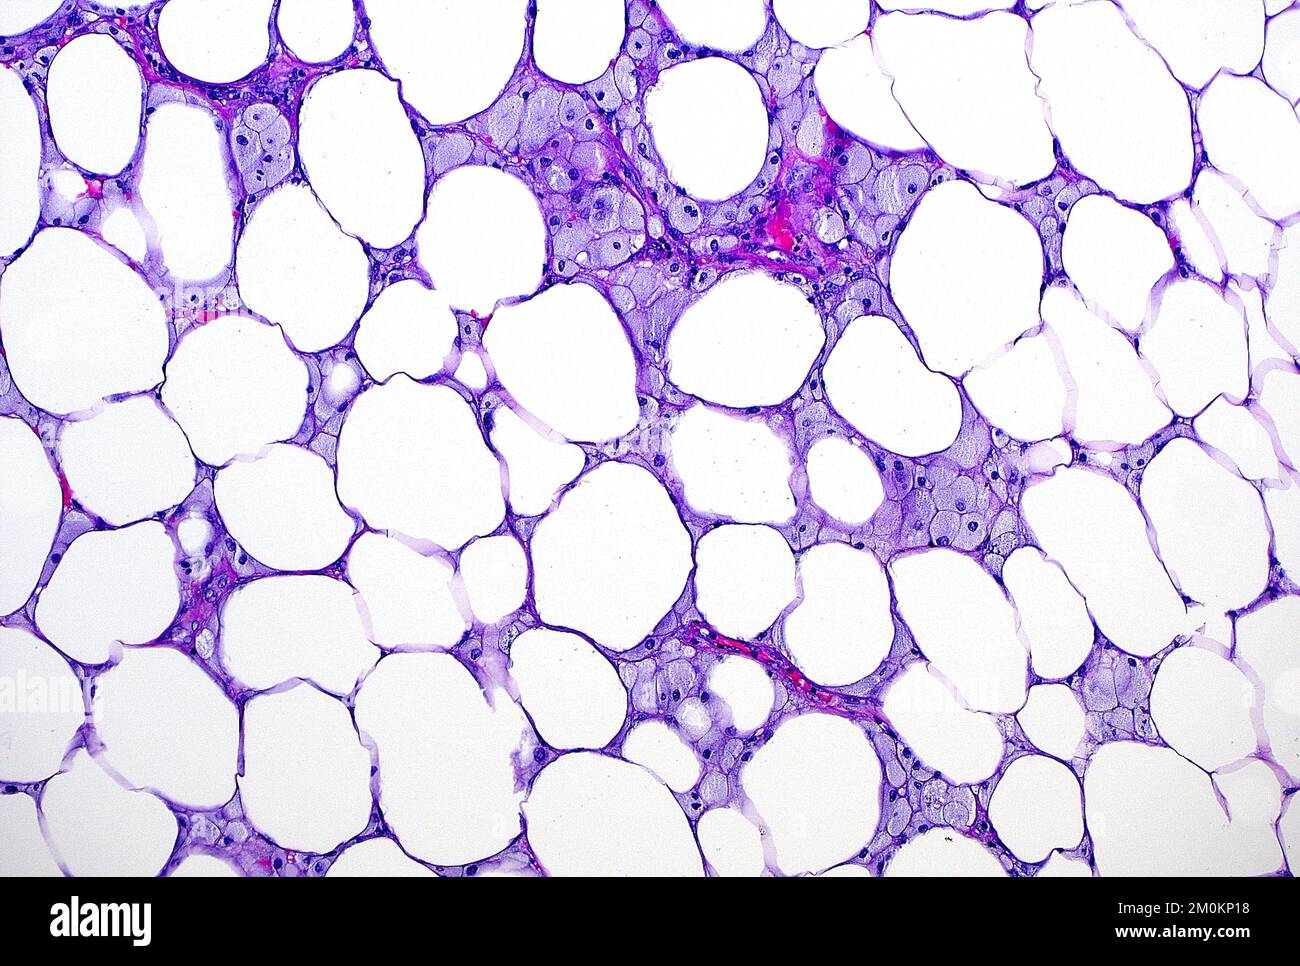

Fat Necrosis Histology

From www.alamy.com

Fat necrosis, light micrograph. Fat necrosis is a destruction of fat Mayo Clinic Fat Necrosis I have lumps where lymph nodes are that are sore. Those increases plus the receiver operating characteristic curve. I know there are ways to produce more definitive mri readings in cases where it might be fat necrosis and not malignancy. But liposarcoma can begin in the. Fat necrosis is often triggered by an event that damages the affected tissue area,. Mayo Clinic Fat Necrosis.

Fat Necrosis Histology Mayo Clinic Fat Necrosis Fat necrosis is necrosis that occurs in parts of the body that contain a lot of fatty tissue, such as the breast. Fat necrosis is death of fat tissue due to injury and loss of blood supply. Sclerosing mesenteritis (sm), an idiopathic nonneoplastic condition affecting 0.18% to 3.14% of the population, is characterized by chronic fat necrosis, inflammation, and. I. Mayo Clinic Fat Necrosis.

From mungfali.com

Fat Necrosis Histology Mayo Clinic Fat Necrosis Fat necrosis is necrosis that occurs in parts of the body that contain a lot of fatty tissue, such as the breast. Those increases plus the receiver operating characteristic curve. I know there are ways to produce more definitive mri readings in cases where it might be fat necrosis and not malignancy. But liposarcoma can begin in the. It can. Mayo Clinic Fat Necrosis.

From mavink.com

Fat Necrosis Histology Mayo Clinic Fat Necrosis It most often begins as a growth of cells in the belly or in the arm and leg muscles. I know there are ways to produce more definitive mri readings in cases where it might be fat necrosis and not malignancy. Fat necrosis is often triggered by an event that damages the affected tissue area, such as injury, surgery, or. Mayo Clinic Fat Necrosis.